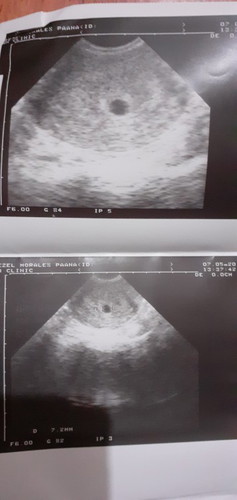

5 weeks pregnant

Hi mga momsh napapraning kasi ako dahil nagpatranV ako last May 7 then no yolk sac pa daw sabi ng sonologist maaga p daw dahil less than 5weeks pa lang daw pero may gestational sac naman na.by the way 1st day mens ko last month April 4..then nagPT me twice positive naman.. okay na din sana isip ko then kahapon kung friend ko nagkwento about blighted ovum kasi may kwork sya na ganun though 12weeks na yun nshare nya lang naman din.. pero now nappraning lang ako.. palagay nyo po ba mga momsh.. ultrasound for less than 5 weeks pregnant?

Saken momsh nung 5 weeks sac pa lang din.. wla pang embryo, pinabalik din ako after 2 weeks.. pagbalik ko meron na embryo tas may heartbeat na din at 7 weeks 1 day. Pray lang.